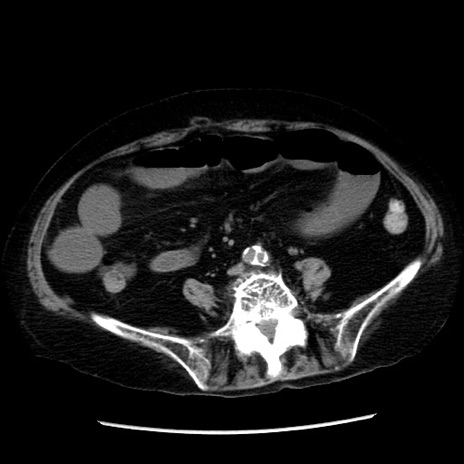

症例

冠状断像